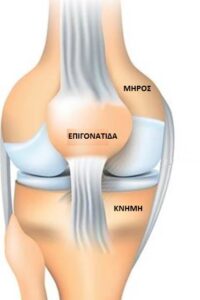

Είναι η δεύτερη μεγάλη άρθρωση του κάτω άκρου, μετά από αυτήν του ισχίου. Τρία οστά, ο μηρός, η κνήμη και η επιγονατίδα (εικόνα 1 ) και πολλαπλοί σύνδεσμοι (εικόνα 2 ) δημιουργούν αυτήν την άρθρωση.